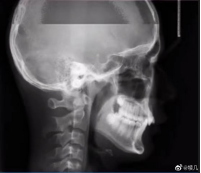

拍牙片時打了個哈欠,變成了毒液?用3D打印技術制作牙齒的好處

小編看到牙片表示:恐怖片果然來源于生活。有網(wǎng)友會問3D打印技術能制作牙齒嗎?小編告訴你:可以!那么用3D打印技術做牙齒有哪些好處呢?